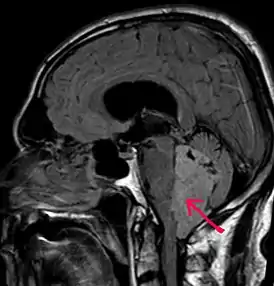

![]() МРТ больного с эпендимомой IV желудочка в Т1-взвешенном режиме. Опухоль отмечена стрелкой | |

Магнитно-резонансная томография

В типичных случаях на МРТ эпендимомы видны в виде объёмных образований, которые заполняют, а иногда и полностью тампонируют полость IV желудочка и распространяются в большую затылочную цистерну или боковую цистерну моста. Солидная часть новообразования на Т1-взвешенных томограммах выглядит изо- или даже гипоинтенсивной и гиперинтенсивной на Т2-взвешенных томограммах[24].

Дифференциальная диагностика эпендимом с другими глиомами основывается в основном на их локализации и топографии, а не на различиях интенсивности сигнала или степени контрастного усиления[25]. Кистозный компонент имеет гипоинтенсивный сигнал на Т1-взвешенных МРТ и гиперинтенсивный по отношению к мозгу на изображениях, взвешенных по Т2. Гетерогенность структуры опухоли обусловлена наличием кист, петрификатов, опухолевой сосудистой сети. После введения контраста отмечается негомогенное усиление средней интенсивности[26]. Дифференциальную диагностику эпендимом боковых желудочков необходимо проводить с медуллобластомами и астроцитомами[23].